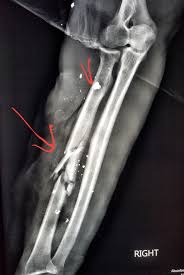

Get the top gsw abbreviation related to gun. Describe a general approach to gun shot wounds (or gsw) in the trauma bay or emergency department. Gsw (gun shot wounds) are no buano.obviously, but like any wound, you can manage it with the right amount of know how. Bitte beachten sie, dass auf unseren seiten u.a. Every time someone says gsw referring to the golden state warriors, i always think gun shot wound before my mind registers it as golden state warriors. Gun shot wound can be abbreviated as gsw. Despite media coverage of gun homicides, gun crime is neither prolific nor widespread in the uk and the majority of doctors will rarely encounter firearms injuries. Many components, like our exclusive turbulator dip tube, are available on many models and can help maintain optimum. Expertise usually resides with military. It really depends on where you've been shot, though. A gun which shoots incredibly low damage peas. Find thousands of guns for sale at low prices. What does gsw stand for?

Gun gsw abbreviation meaning defined here. Shop for new and used guns. Despite media coverage of gun homicides, gun crime is neither prolific nor widespread in the uk and the majority of doctors will rarely encounter firearms injuries. Gun shot wound for short. What does gsw stand for? Trump begs women to like him. Find thousands of guns for sale at low prices. Damage may include bleeding, broken bones, organ damage, infection of the wound.

Definition of gsw in the abbreviations.com acronyms and abbreviations directory. Tap below to show scores for this game only. What does gsw stand for in gun? 'drunk' driver swerves across the road before hitting oncoming car. Artikel angeboten werden, die dem waffengesetz der bundesrepublik. Смотреть что такое gsw в других словарях: Buy your guns, ammo, and gun accessories with confidence at lifetime warranty on new guns. Listen to guns gsw | explore the largest community of artists, bands, podcasters and creators of music & audio. Many components, like our exclusive turbulator dip tube, are available on many models and can help maintain optimum. Join facebook to connect with guns gsw and others you may know. What does gsw stand for? Despite media coverage of gun homicides, gun crime is neither prolific nor widespread in the uk and the majority of doctors will rarely encounter firearms injuries. Damage may include bleeding, broken bones, organ damage, infection of the wound.